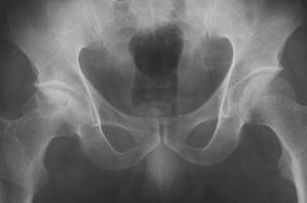

找到骶裂孔,嚴(yán)格消毒鋪孔巾,普魯卡因局部浸潤麻醉后,用9號腰穿針與骶骨成30°~45°角刺入約4.5~5.5cm,拔出針芯如無腦脊液流出即可注入藥液。注入速度要慢,約2~3min注完。

但最多不超過5次。穿刺注意事項:骶裂孔與珠網(wǎng)膜下腔終端的距離最長約75mm,最短為19mm,平均約47mm,故穿刺針不要進(jìn)入骶管內(nèi)過深,以免刺入珠網(wǎng)下腔引起不良后果。

骶管腔容積最小12ml,最大65ml,平均30ml,故注入藥液最大劑量不宜超過30ml。